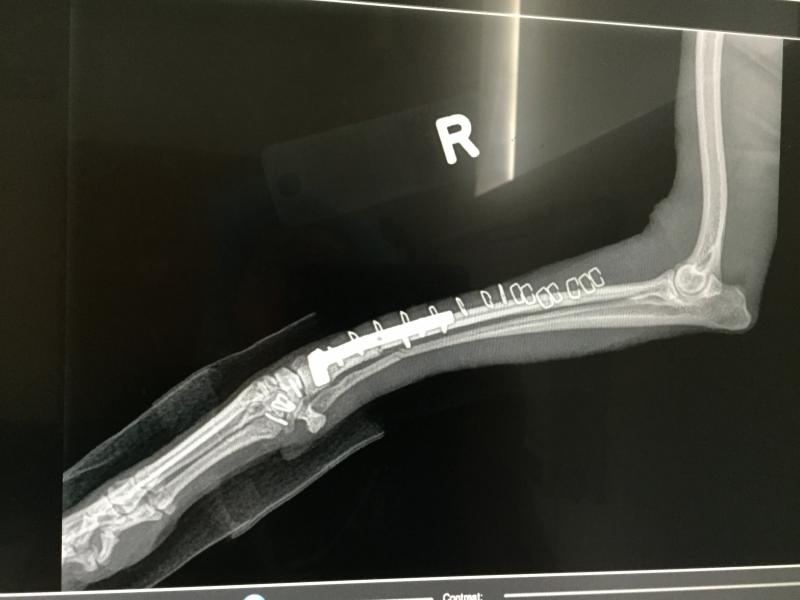

Radius ulna fracture, Italian greyhound

Orthopedic repair, canine hit by car, hind legs fractured